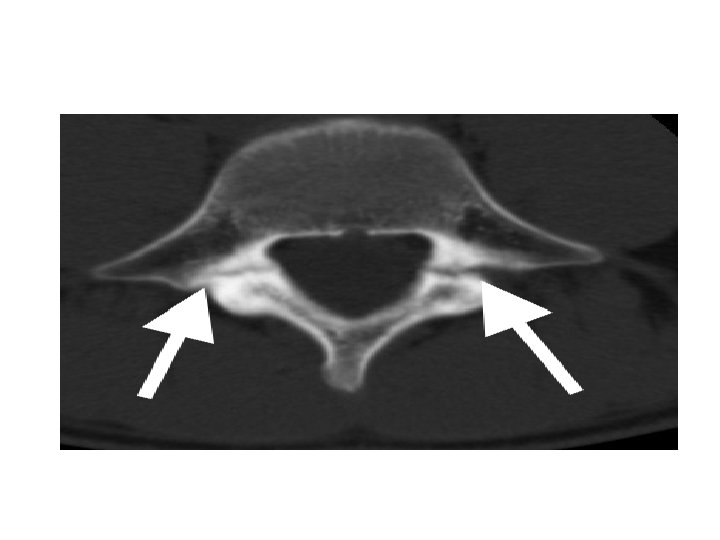

• Degenerative : 25% - Typically in middle aged women ( H. factors). - Location : mostly at L 4/L 5. - Etiology : degeneration ( with OA , crystal arthropathy) in the facets and disc with intact lamina … here there is no pars interarticularis defect. - This can be worsened by the presence of congenitally sagittal facet joint orientation.

• Pathophysiology : - The forward slip of the vertebral body here is mainly allowed by I. D degeneration and facet joint degeneration. - disc degeneration leads to facet capsule degeneration and microinstability … with further degeneration >> macroinstability.

- neurologic symptoms caused mainly by central and lateral recess stenosis and to a less degree foraminal stenosis. § Central and lateral recess stenosis : • degenerative slip at L 4/5 will affect the descending L 5 nerve root in the lateral recess. - caused by slippage, hypertrophy of ligamentum flavum, and encroachment into the spinal canal of osteophytes from facet arthrosis.